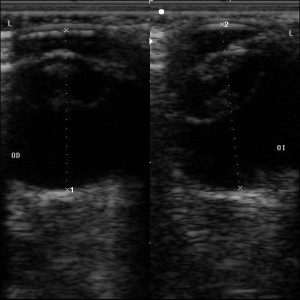

Ecografia OcularLa ecografía ocular es una técnica de diagnóstico rápida y sencilla, la que nos permite evaluar el ojo, sus estructuras internas y externas, por detrás del globo ocular. Por lo general están indicadas cuando hay opacidades corneales que no permiten evaluar el ojo internamente, y así por medio de la ecografía conocer el estado del cristalino, la retina, la presencia de tumores y hemorragias internas (en casos traumáticos) tambien de sospecha de cuerpos extraños, tumores y afecciones retro bulbares.